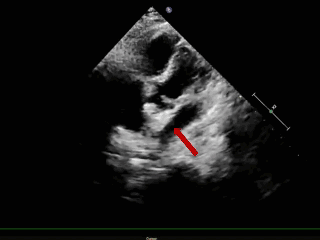

成型锁定

四腔心切面

主动脉短轴切面

封堵器呈“Y”字形牢牢抱住主动脉,夹持缺损